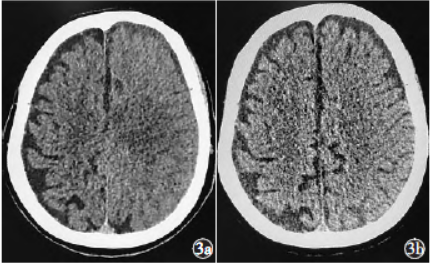

图3碘克沙醇致全脑血管造影术后对比剂脑病患者首次造影术后头部CT影像资料3a为术后4h头部CT影像,示左侧大脑半球脑回肿胀,脑沟脑裂变窄;3b为术后48h头部CT影像,示脑水肿明显减轻